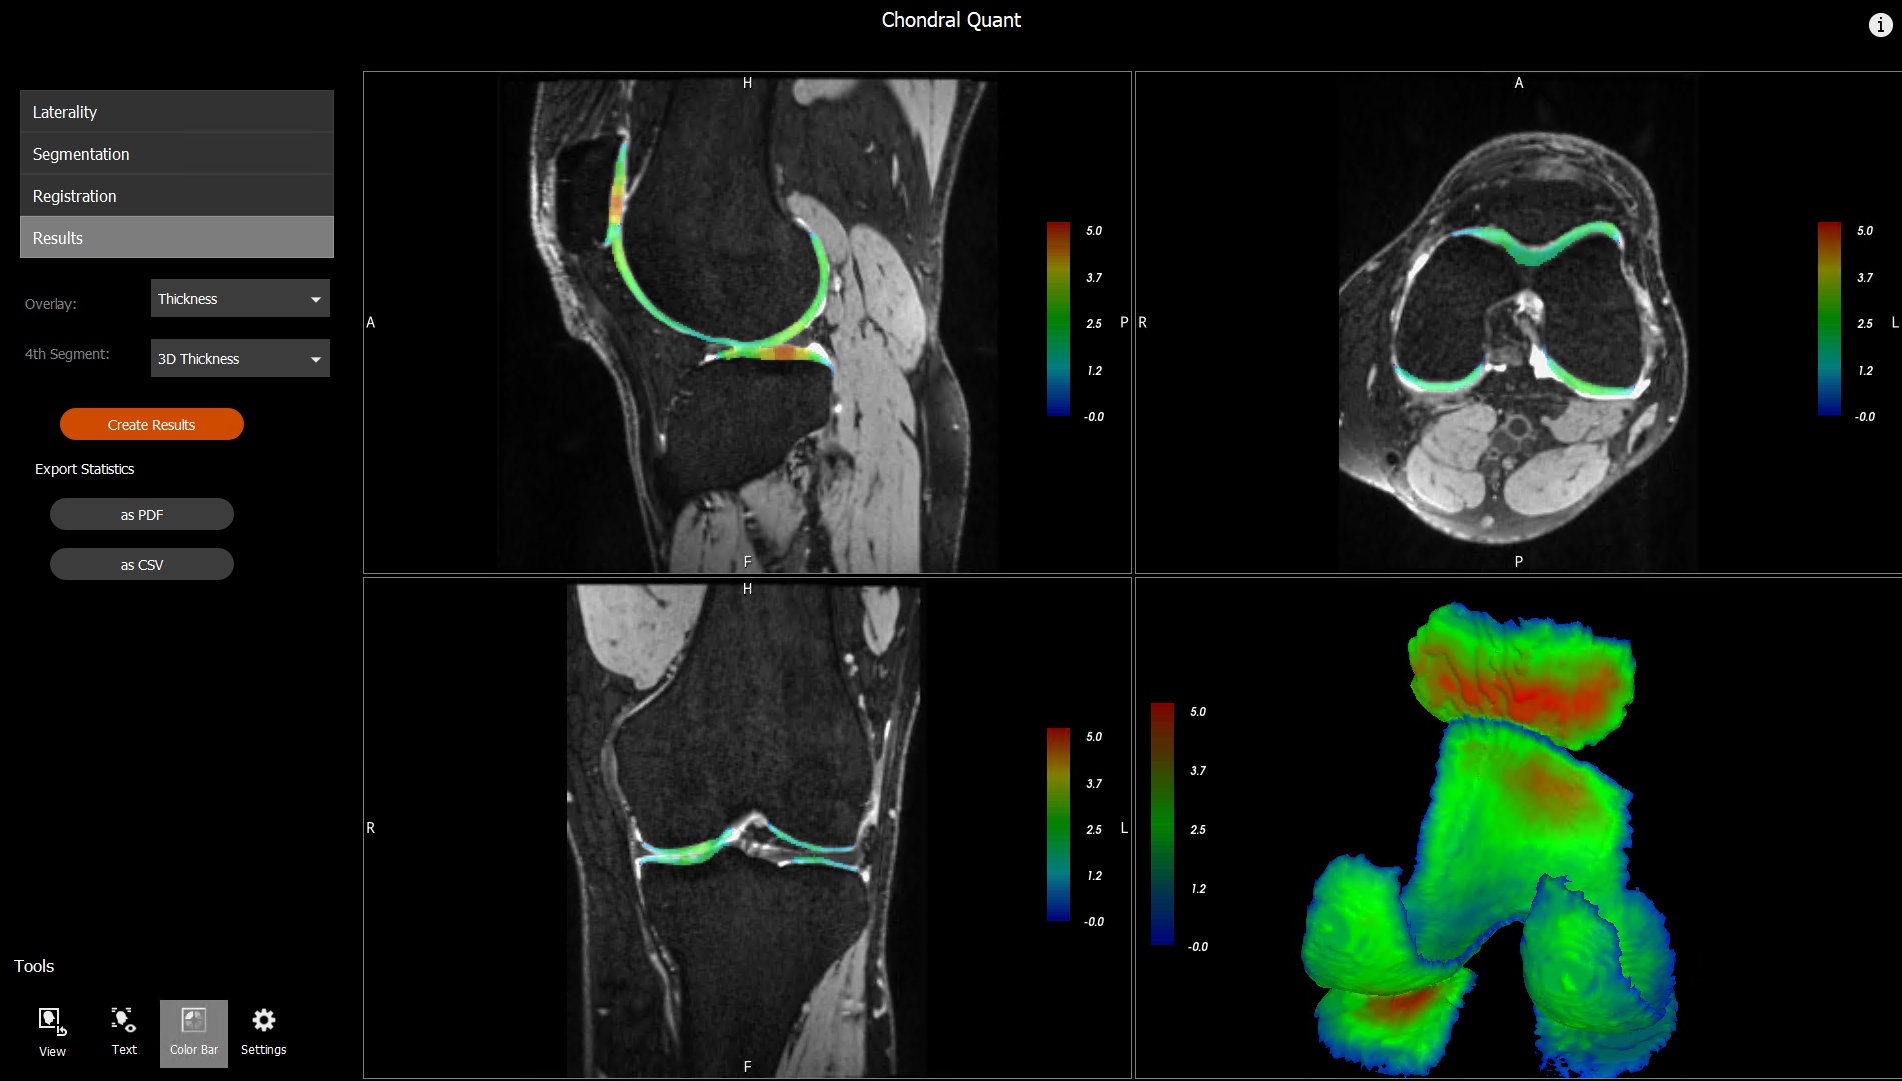

There is much that medical science doesn’t know about osteoarthritis in the knee, but researchers at The University of Queensland (UQ) – in partnership with the CSIRO and Siemens Healthineers – have developed a software tool called Chondral Quant that could change that.

“Then our machine learning algorithm identifies the key aspects of the knee that are important to the disease. We identify the different regions of interest within the knee – the bones, the cartilage and all the bits that are important in osteoarthritis.”

The Chondral Quant software processes the MRI automatically: the algorithm does the heavy lifting and is significantly quicker than its human counterparts.

Chondral Quant’s quantitative analysis not only documents the volume and thickness of cartilage, it allows for a full exploration of its physiology.

It can look at the biochemical makeup of the tissue, assessing how much water is in the cartilage and identifying proteins and other molecules that could be of clinical significance to a condition like osteoarthritis. These can then be explored at scale and speed.